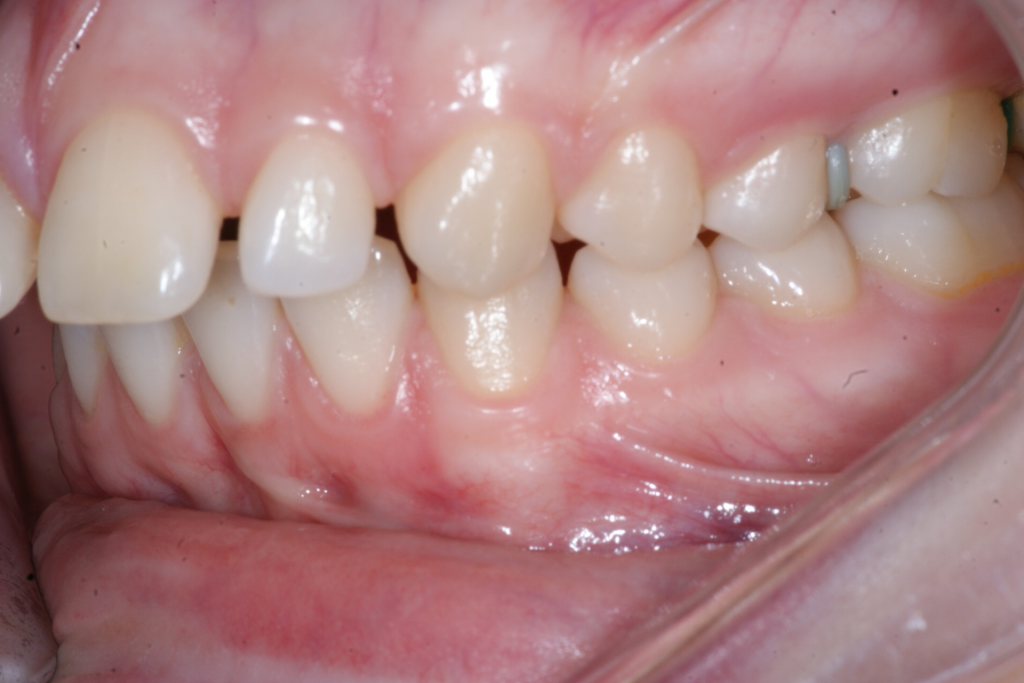

Correction d’une malocclusion de type Classe II division 1 avec excès d’espace aux 2 arcades.  Des appareils fixes (boîtiers) et une expansion palatine furent nécessaires pour améliorer ce sourire.  Traitement chez une adolescente, réalisé en 26 mois.